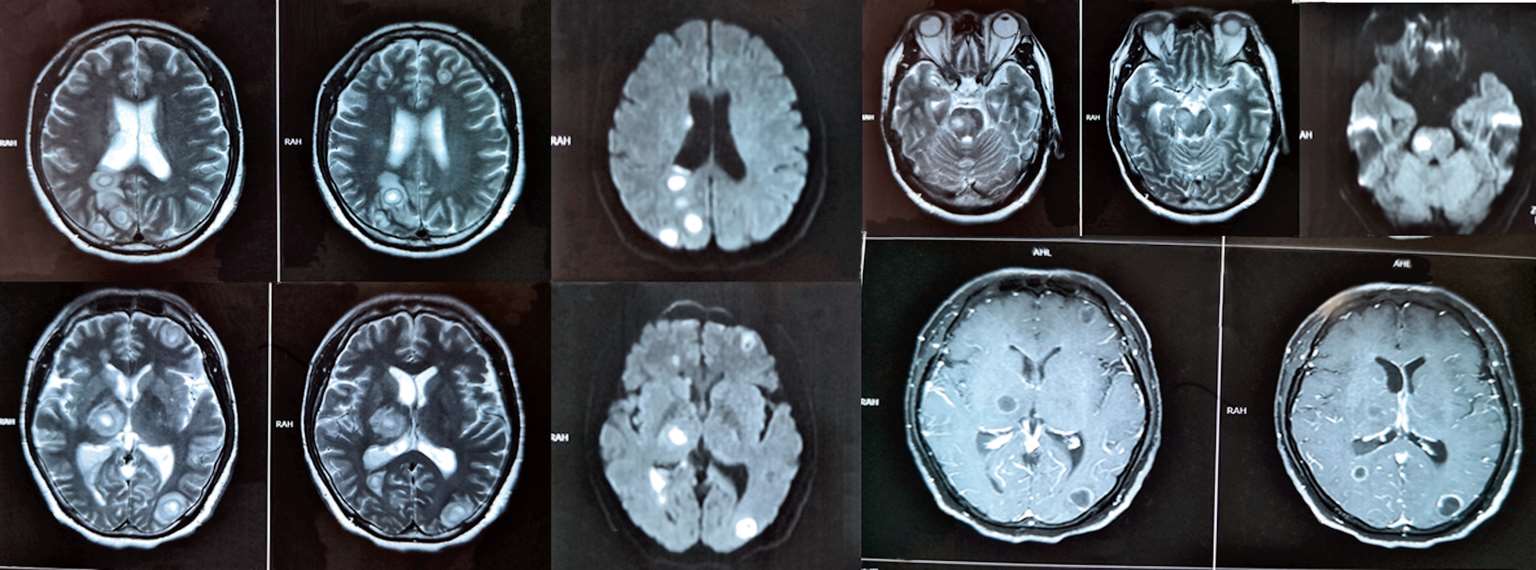

江苏省当地人民医院7月13日行腰穿检查,脑脊液葡萄糖1.33 mmol/L(↓),蛋白质2 644.5 mg/L(↑),脑脊液有核细胞数150×10 6 /L(↑),多核细胞25%。头颅增强MRI(图2-3)示“脑实质内、右侧侧脑室后角内多发异常信号影,考虑感染性病变可能”。入院后予甘露醇、甘油果糖脱水,呋塞米、螺内酯利尿,哌拉西林/他唑巴坦、万古霉素、美罗培南抗感染,地塞米松(共5 mg)抗炎等治疗后,患者症状仍逐渐加重,仍有高热,四肢不自主颤动,进食后有呛咳,大小便失禁,意识障碍进一步加深,呈昏迷状态,双下肢肌力肌张力明显减退,于7月14日出院至我院急诊留观。

图2-3 2018年7月13日头颅增强MRI:脑实质内、右侧侧脑室后角内多发异常信号影,考虑感染性病变可能

该患者以发热伴意识障碍起病,外周血白细胞及中性粒细胞比例明显升高,进一步检查发现颅内多发占位,DWI呈明显高信号,周围见水肿信号,增强后病灶呈环形强化;胸腰髓占位,增强病灶亦呈环形强化;肺内病灶伴空洞形成,肝脾也发现多枚低密度影,并发现左肾占位。腰穿查脑脊液中白细胞及蛋白质升高、糖降低,故首先考虑播散性感染可能大,转移性肿瘤待排。由于患者入院时症状及体温均有所好转,故继续坚持诊断性抗结核治疗,方案为:异烟肼0.6 g ivgtt qd,利福平0.45 g ivgtt qd,乙胺丁醇0.75 g po qd,阿米卡星0.6 g ivgtt qd,利奈唑胺0.6 g ivgtt q12h。